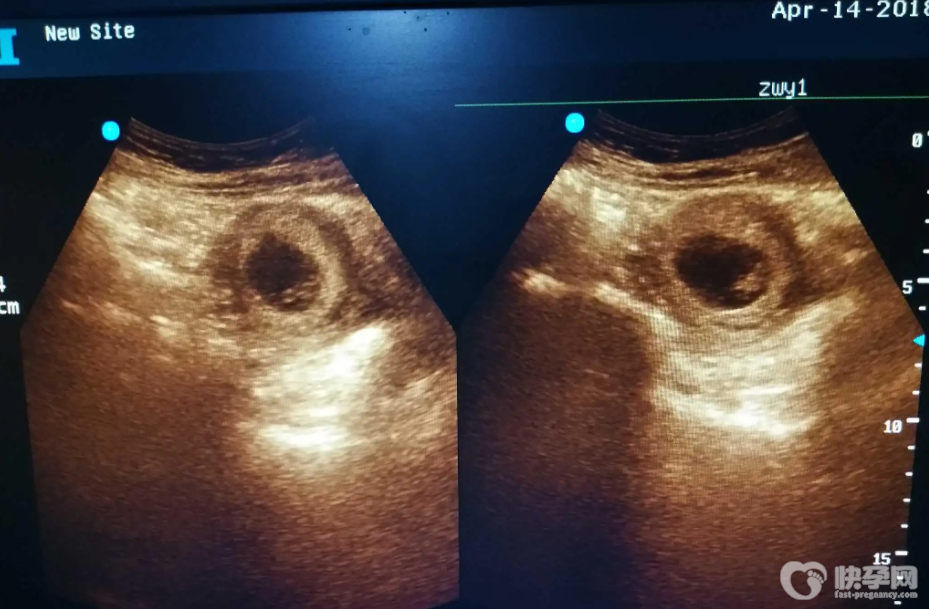

血块和孕囊的区别图分享,从颜色和形状上即可准确分辨

血块和孕囊的四个区别图解,轻松学会分辩血块和孕囊

很多女性怀孕后发现下半身排出了很多血块,非常担心孕囊流出,担心自己流产了。一般情况下,如果确定孕囊排出,就说明女方已经流产了,这种情况一般发生在药物流产后。此外,怀孕..

孕囊和血块怎么辨别?血块和孕囊的区别图

对于怀孕早期的女性,如果发生自然或者药物流产,那么就需要注意观察血块和孕囊的区别,以此来确定是否出现了流产的征兆,避免造成严重的后果,小编就为大家总结了具体的分..